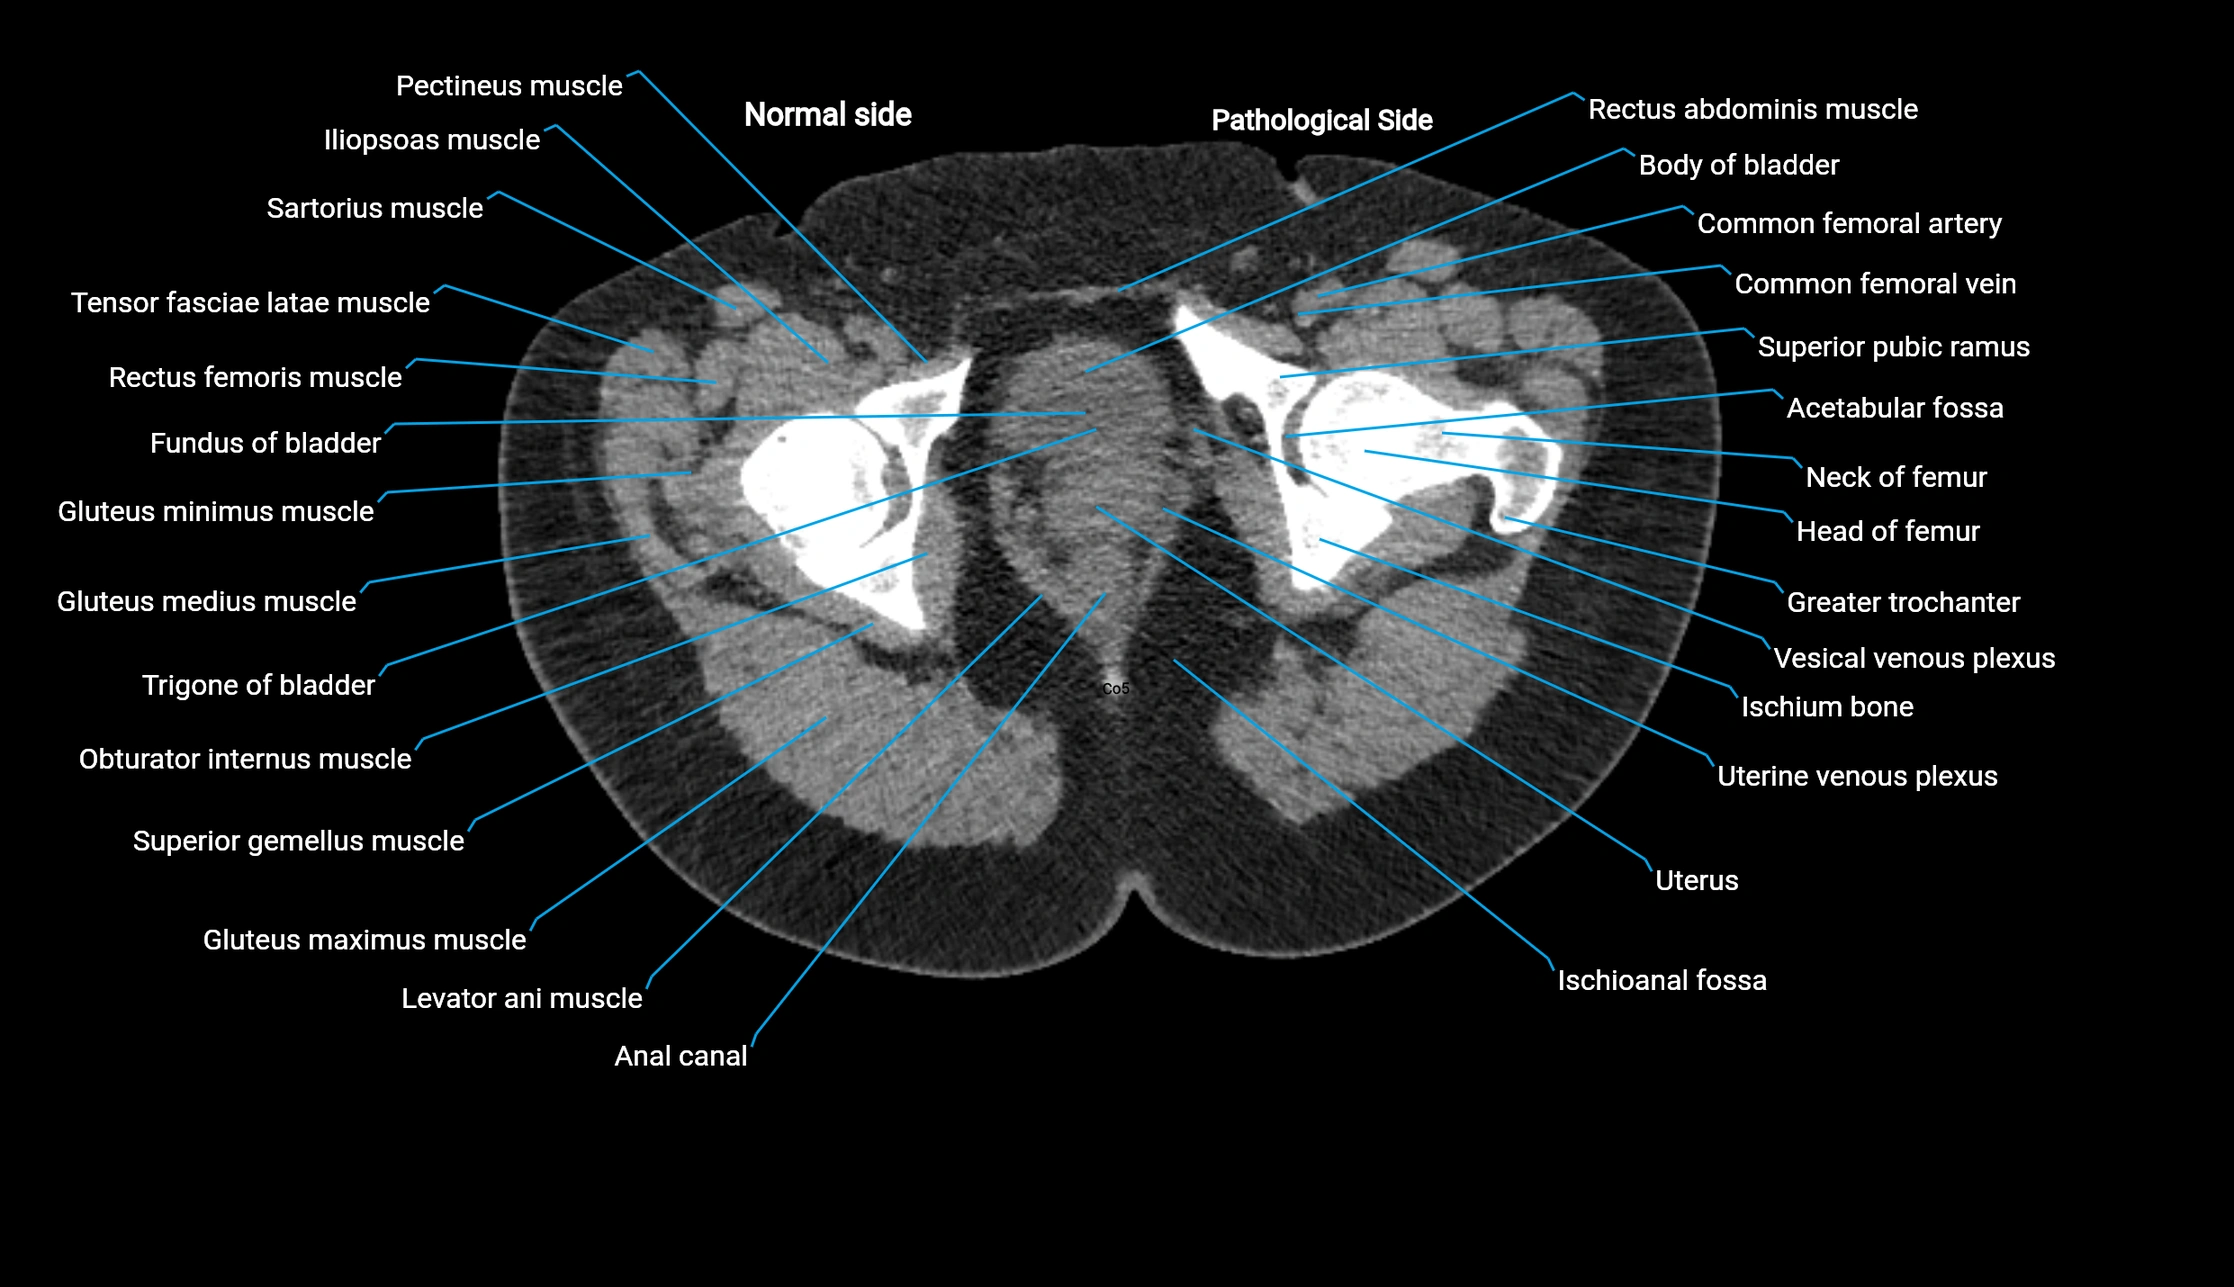

CT Appearance

Non-contrast CT:

• Demonstrates cortical bone of acetabular rim in excellent detail

• Detects fractures, dysplasia, retroversion, or bony overcoverage (pincer impingement)

• 3D reconstructions used in preoperative hip surgery planning

CT Post-Contrast (CT Arthrography):

• Joint contrast outlines the acetabular labrum, cartilage, and margin

• Demonstrates labral tears, cartilage defects, and subtle bony abnormalities

• Alternative to MR arthrography in patients with MRI contraindications